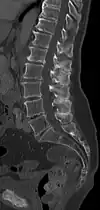

A diagram of a human vertebral body. With Baastrup's sign, the posterior spinous process, pointing down and to the left, is abnormally thickened due to repetitive microtrauma. | |

Baastrup's sign is an orthopedic and radiographic disorder that often occurs in elderly humans. It is characterized by enlargement of the posterior spinous processes of the lumbar spine, with normal intervertebral disc height and neuroforamina. The reason it is referred to as kissing spine is because the posterior spinous processes 'kiss' and touch one another as the individual goes into lumbar extension, for example when flat on their stomach.[1][2] The condition has been seen in humans, canines, particularly with boxer breeds,[3] and certain breeds of horses.[4] This disorder is named after Christian Ingerslev Baastrup.

The salient feature of the disorder is the exuberant osteophytosis that occurs at posterior lumbar spinous processes. Osteophytes are coarse calcifications at the edges of bone that form due to repetitive stress and trauma. There is also atrophy and fatty replacement of paraspinal musculature, which can be detected by CT or MRI.[5]